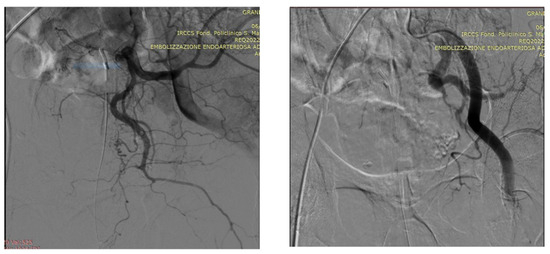

Technical Details of PAE